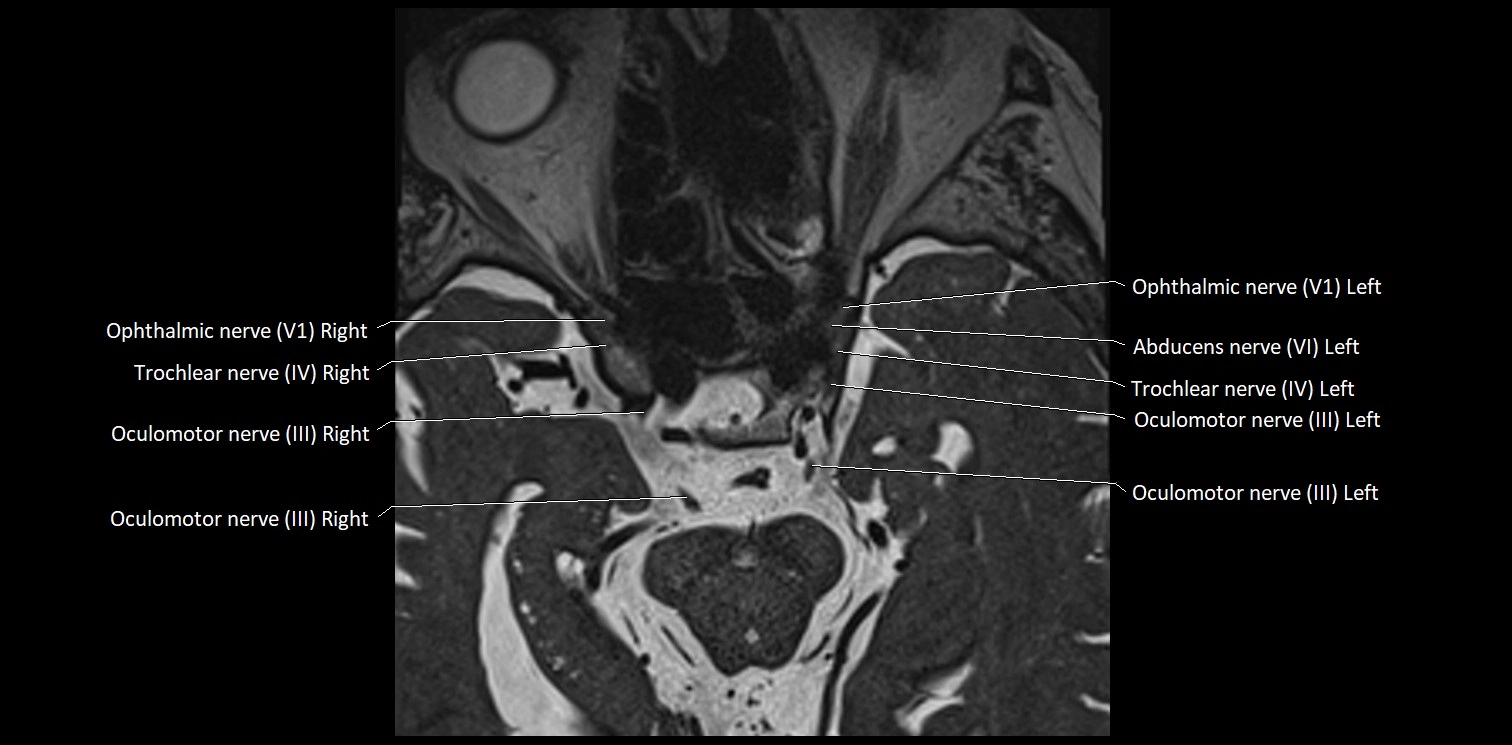

MRI Appearance

• The abducens nerve is a small, thin, linear structure

• Best visualized on high-resolution T2-weighted 3D MRI sequences (e.g., FIESTA or CISS)

• Seen as a hypointense (dark) line running from the brainstem at the pontomedullary junction, traversing the prepontine cistern, and entering Dorello’s canal under the petrosphenoidal ligament, then into the cavernous sinus, and finally the orbit

• May be challenging to visualize in standard MRI due to its small size

• Pathology may be inferred by absence, displacement, or enhancement of the nerve

MRI images

image